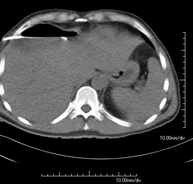

- TC Abdomen

Prova diagnòstica que consisteix en l'estudi de l'abdomen d'alta definició anatòmica (fetge, vesícula biliar, via biliar, pàncrees, melsa, estómac, intestins, ronyons, estructures vasculars, bufeta, úter i ovaris, etc.) mitjançant l'ús d'un equip de TC (Tomografia Computeritzada). Aquestes imatges s'estudien posteriorment en una estació de treball que permet obtenir reconstruccions bidimensionals en diferents plànols de l'espai i també reconstruccions 3D (volumètriques). La majoria d'estudis requereixen l'ús de contrast iodat per millorar la definició de les imatges. - TC Pelvis